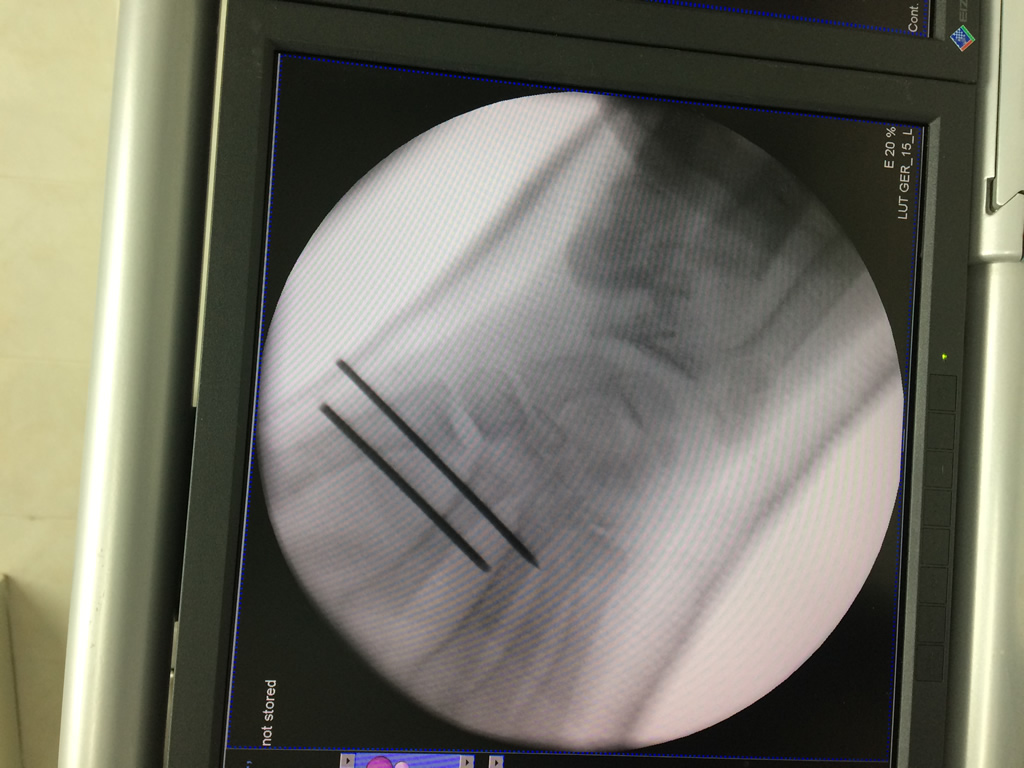

Cirugías de Húmero - Cirugías de Muñecas y Manos

Los procedimientos más comunes en cirugía de la mano son aquellos destinados a reparar traumatismos, incluyendo lesiones de tendones, nervios, vasos sanguíneos, y articulaciones; huesos fracturados; y quemaduras, cortes, y otros daños de la piel.